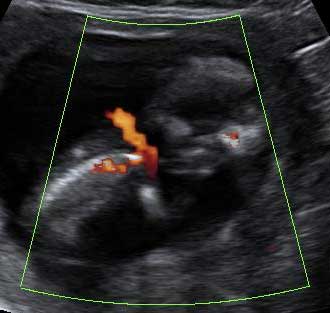

Este bebé de 12 semanas de gestación, pone su mano en el campo de visión del ecógrafo. Por eso el especialista, comenta que "en condiciones favorables, como en este caso, pueden individualizarse los dedos". Efectivamente, podemos contar los cinco dedos del bebé, que se señalan con números en la imagen.